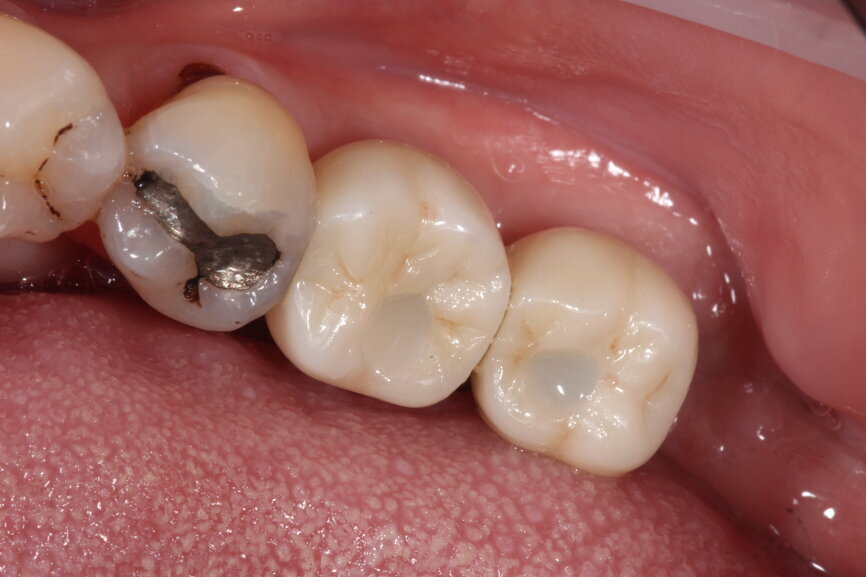

Even with assisted surgery or guided surgery, there are sometimes certain restrictions that prevent us from achieving the most ideal implant placement, such as this case shown where posterior access in the second molar region was reduced, so achieving the perfect parallel was extremely difficult.